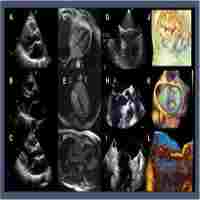

| Abstract | BACKGROUND Current guidelines recommend mitral valve surgery for asymptomatic patients with severe degenerative mitral regurgitation and preserved left ventricular systolic function when exercise pulmonary hypertension (PHT) is present. However, the determinants of exercise PHT have not been evaluated. The aim of this study was to identify the echocardiographic predictors of exercise PHT and the impact on symptoms. METHODS AND RESULTS Comprehensive resting and exercise transthoracic echocardiography was performed in 78 consecutive patients (age, 61+/-13 years; 56% men) with at least moderate degenerative mitral regurgitation (effective regurgitant orifice area =43+/-20 mm(2); regurgitant volume =71+/-27 mL). Exercise PHT was defined as a systolic pulmonary arterial pressure (SPAP) >60 mm Hg. Exercise PHT was present in 46% patients. In multivariable analysis, exercise effective regurgitant orifice was an independent determinant of exercise SPAP (P<0.0001) and exercise PHT (P=0.002). Resting PHT and exercise PHT were associated with markedly reduced 2-year symptom-free survival (36+/-14% versus 59+/-7%, P=0.04; 35+/-8% versus 75+/-7%, P<0.0001). After adjustment, although the impact of resting PHT was no longer significant, exercise PHT was identified as an independent predictor of the occurrence of symptoms (hazard ratio=3.4; P=0.002). Receiver-operating characteristics curves revealed that exercise PHT (SPAP >56 mm Hg) was more accurate than resting PHT (SPAP >36 mm Hg) in predicting the occurrence of symptoms during follow-up (P=0.032). CONCLUSIONS Exercise PHT is frequent in patients with asymptomatic degenerative mitral regurgitation. Exercise mitral regurgitation severity is a strong independent predictor of both exercise SPAP and exercise PHT. Exercise PHT is associated with markedly low 2-year symptom-free survival, emphasizing the use of exercise echocardiography. An exercise SPAP >56 mm Hg accurately predicts the occurrence of symptoms. |